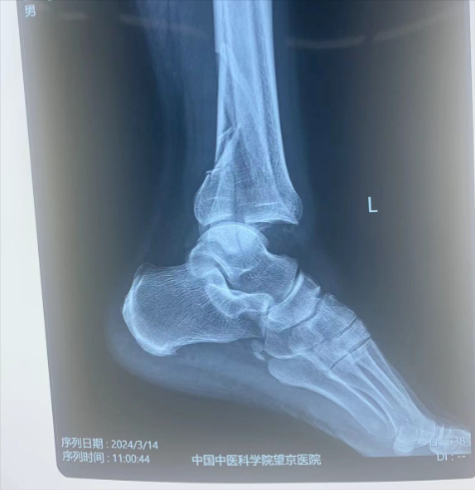

本病例左三踝骨折。術(shù)前正側(cè)位片:脛骨遠(yuǎn)端骨折。

術(shù)前X光片: